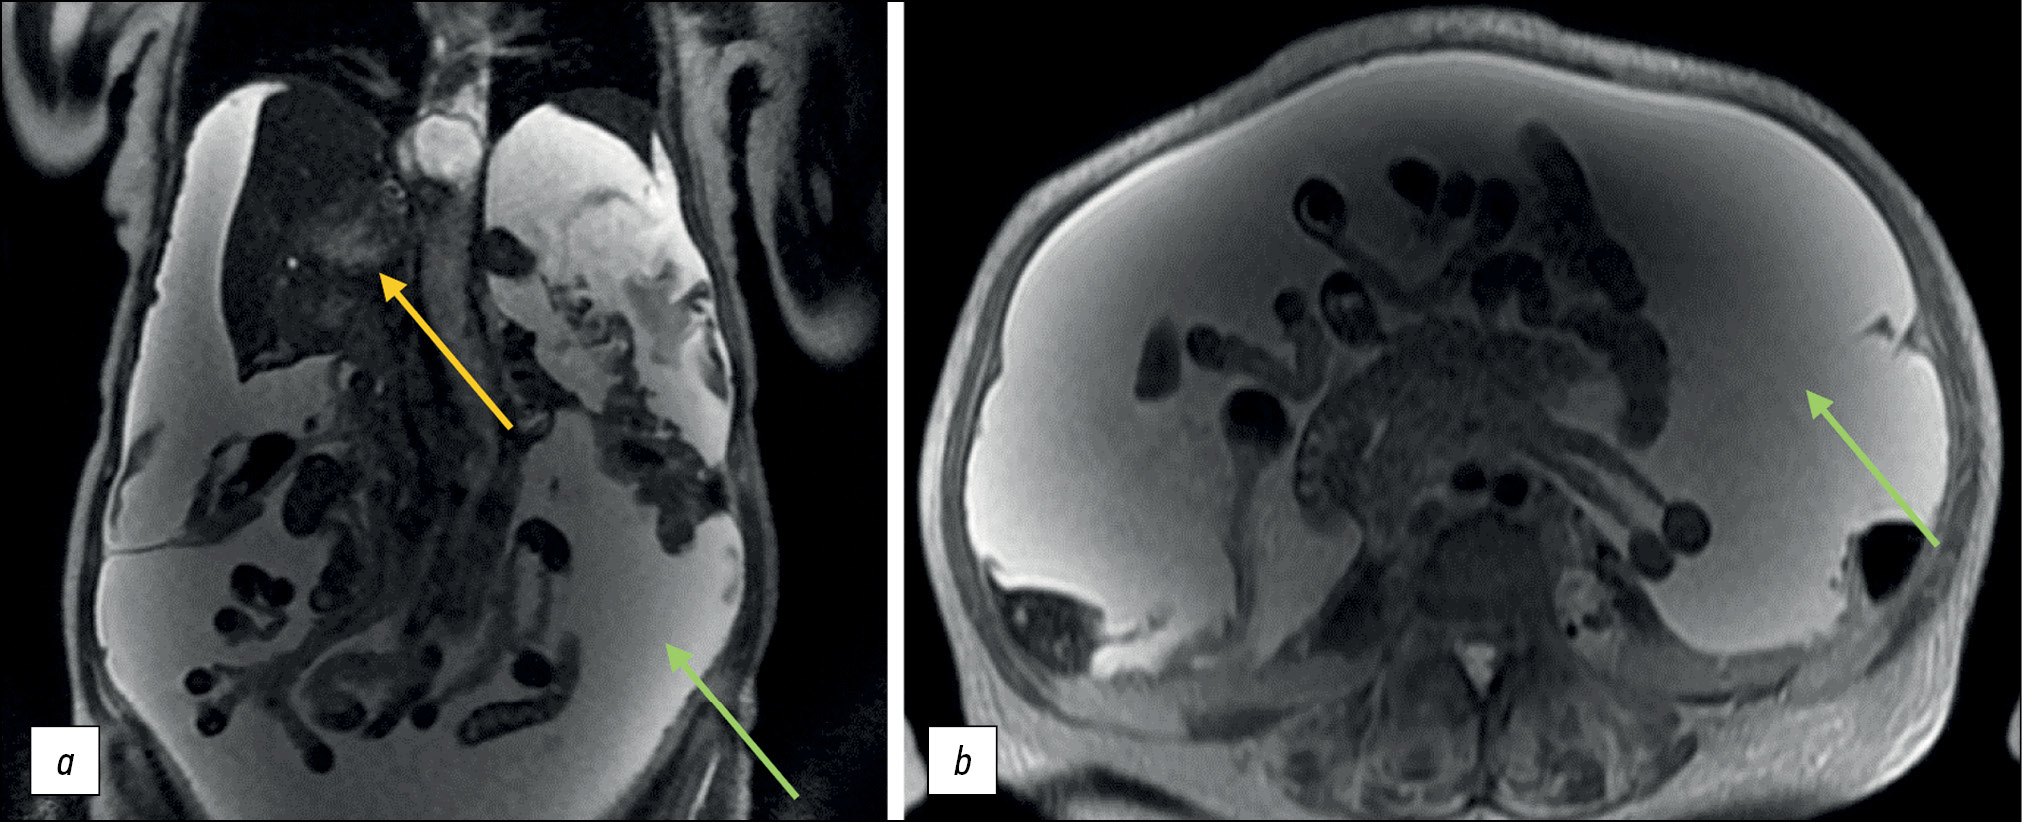

Standard T2-WIs are taken in the frontal and axial planes using SE. These sequences have a relatively long acquisition time but provide a high SNR. The routine use of this approach in abdominal radiology is limited by the patient’s breathing, pulsation of large vessels, and intestinal motility. In such cases, respiratory gating can be performed, which increases scan time (up to 5–7 min); however, motion correction is not absolute: in most cases, there is a blurring effect at the border of organs, which can make diagnosing various pathologies difficult. As a result, T2-WIs are now more commonly obtained using accelerated fast SE, single-shot accelerated fast SE or steady-state free precession sequences (Fig. 5).

Figure 5. Single-shot fast spin-echo mode: hepatocellular carcinoma with inferior vena cava invasion (yellow arrow) and tense ascites (green arrow): а coronal plane; b axial plane.

Images can be taken with or without breath-holding. When taking images without breath-holding, every effort should be made to reduce respiratory motion artifacts by multiple signal averaging and/or respiratory compensation/triggering. The main difference between this and standard SE is the relative decrease in tissue contrast, which can lead to diagnostic errors, particularly small changes compared with unaffected parenchymal organ tissue (e.g., small hepatocellular carcinoma). Conversely, T1-WIs compensate for this disadvantage: these areas, on average, have a longer T1 time relative to the unaffected tissue and are well visualized on nonenhanced SGE sequences or early (arterial) postcontrast images as focal lesions with a reduced signal.